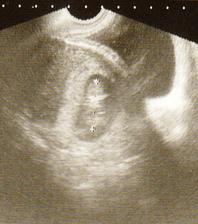

2.9. UTZ dopadl výborně. Máme 6,5cm, mimísek se poctivě ukazoval, dost v bříšku řádil. Máme všechno co máme mít, nic nechybí ani nepřebývá🙂 Další kontrola v poradně bude 30.9. a UTZ až 4.11.:( Už teď se s tatínkem těšíme, až prcka zase uvidíme;)